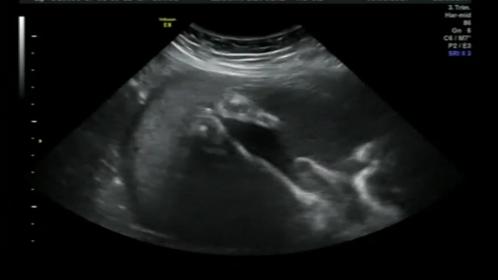

Please could you have a look and see if you can tell what this us. We are not finding out the sex as my boyfriend doesn't want to know but at our 30 wk 4d scan before putting into 4d i see this in 2d. It is the baby's feet but also looks likes a boy part and outline of bum.. what do you think? Baby boy or gal?Attachment 37332Attachment 37332